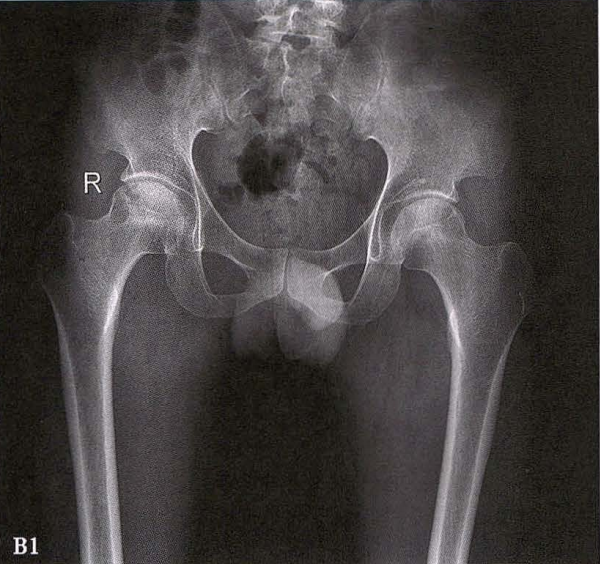

(1)X线检查 X线是诊断股骨头坏死的首选检查手段,常规拍摄髋关节正侧位片。早期股骨头坏死X线片可正常或显示股骨头外上方骨小梁稀疏;病情进展后逐渐出现密度增高、硬化带、囊性变等;晚期则出现股骨头塌陷、关节间隙变窄、Shenton's线不连续、骨关节炎改变等。硬化带和新月征是股骨头坏死X线特征性表现。在股骨头关节面塌陷变形早期上关节间隙不变或增宽后期随着骨关节炎加重关节间隙逐渐狭窄。

B.男性,31岁,双侧股骨头坏死,双侧均为Ⅲ期。X线片示双侧股骨头密度不均、股骨头稍变扁(B1)。MRI(T1加权像)示股骨头内多发不规则信号带(B2),股骨头内凸向大转子的双线征(白色箭)和软骨下骨骨折(白色三角)。